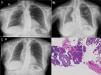

(A) Chest radiograph: infiltrate in right upper lobes. (B) Infiltrates in right upper lobe, right lower lobe and left upper lobe with loss of volume in the right hemithorax. (C) Favorable radiological progress. (D) Computed tomography-guided lung biopsy: inflammatory thickening of the septa with intra-alveolar fibrin balls.

A 72-year-old woman was admitted with a 1-month history of progressive dyspnea, dry cough, low-grade fever, asthenia, anorexia and weight loss. Following a previous chest radiograph, she had been diagnosed with right upper lobe (RUL) pneumonia (Fig. 1A), for which she had received levofloxacin 500mg/day for 7 days, with no improvement. She had no occupational exposure of interest, and no toxic habits. Clinical history included childhood bronchial asthma, mild kidney failure, and hypothyroidism. On admission, her general condition was reasonable, temperature 37.2°C, blood pressure 130/75mmHg, heart rate 69bpm, no shortness of breath, with 92% oxygen saturation while breathing room air. Physical examination revealed dry crackles throughout the right hemithorax and left lung base on auscultation. Chest radiograph showed progression of the RUL infiltrate and loss of volume (Fig. 1B). Clinical laboratory tests showed mild normocytic, normochromic anemia, with leukocytes 11460, ESR 120mm/h, CRP 29.5mg/dl, and a pattern of cholestasis (alkaline phosphatase 389IU/l, GGT 83IU/l) with negative ANA and ANCA.

Suspecting that the slow resolution of the pneumonia was due to unusual pathogens, we started treatment with piperacillin–tazobactam, and a chest CT was performed, revealing extensive consolidations in the posterior regions of the right lung with pulmonary collapse. A bronchoscopy with transbronchial biopsy was performed twice, and was inconclusive on both occasions (chronic inflammatory component and pneumocytic hyperplasia with mild atypia). The patient's clinical situation worsened and radiological signs progressed, so a CT-guided lung biopsy was performed. The endoscopic samples obtained were negative for pathogens, so treatment began with methylprednisolone at a starting dose of 40mg/8h. Clinical progress was exceptional, with frank clinical and radiological improvement after 48h, and radiography returned to normal after one week of treatment (Fig. 1C). Biopsy showed a typical AFOP pattern (Fig. 1D), characterized by inflammatory thickening of the septa and fibrin balls in the alveoli. After 10 months of tapering corticosteroid treatment (now at a dose of prednisolone 10mg/48h), the patient is currently asymptomatic.